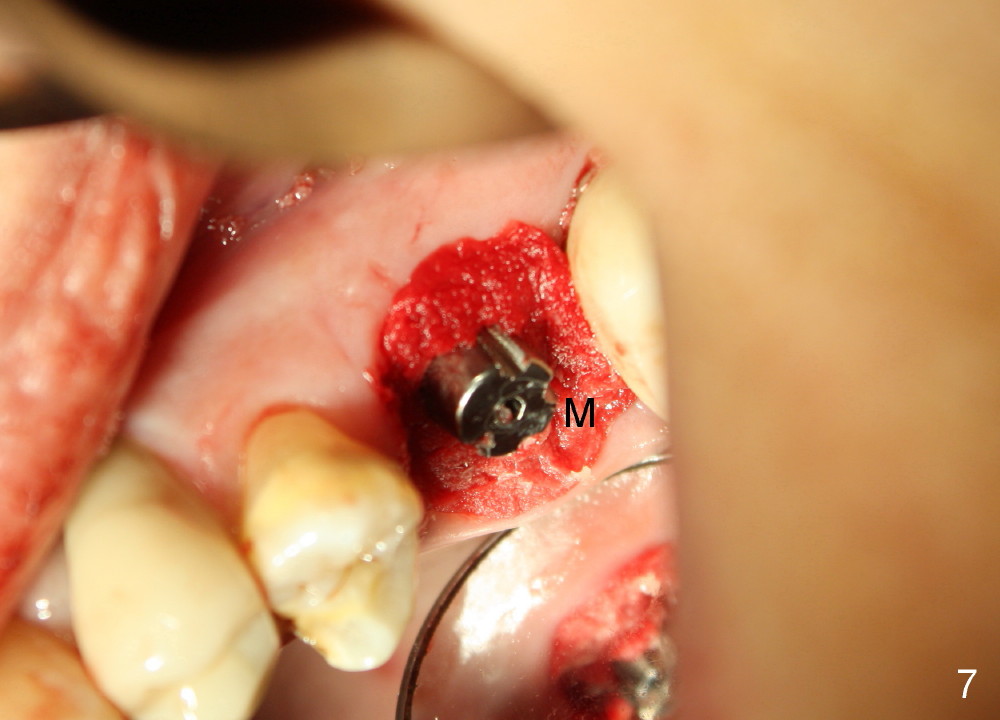

The upper left 1st molar is extracted with sectioning. The septum is large. A surgical fissure bur is used to initiate an osteotomy in the middle of the septum (Fig.1 <; P: palatal socket, MB: mesiobuccal socket), followed by tapping with resistance a 2 mm osteotome ~ 8 mm into the septum. It is tougher to drive 3 mm osteotomy. A 2.5 mm reamer is used to enlarge the osteotomy at 50 RPM at the same depth. Then it is relatively easy to tap 3 and 4 mm osteotomes at ~ 8 mm into the septum. A 4.5x17 mm tap is inserted 8 mm deep with binding to the septum. PA is taken (Fig.2). It appears that the sinus floor (black >) has been penetrated, but the osteotomy has not reached the apex (white >) of the palatal (P) socket. Then the tap is advanced ~ another 3 mm. When the tap is removed, the osteotomy (Fig.3 O) is slightly toward the buccal aspect of the extraction socket, but it has intact wall, including the mesiobuccal (>). The apex of the ostoetomy has no bone, but there is no air leakage. The next tap, 5x17 mm, is inserted shallower (~ 8 mm in the septum; to reduce potential trauma) with stability. However, 6x17 mm tap at the same depth does not obtain stability, since the osteotomy deviates severely mesiobuccally (Fig.4 arrow) with breakdown of the mesiobuccal wall. So the osteotomy has to be deeper in order to achieve stability of 6x17 mm tap (by engaging into more apical bone). A 7x17 mm tap is then intended to be inserted to close the socket as much as possible, but as it is being inserted, the osteotomy is more severely deviated and tilted mesiobuccally with the original mesiobuccal wall further being broken down (not shown). It appears to compromise stability. Mixture of autogenous bone from reamer, allograft and synthetic bone is placed in the mesiobuccal and palatal sockets before placement of the 6x17 mm implant (Fig.5 I). Unfortunately some of graft blocks the apical osteotomy. To clear the blockage, some of previous osteotome and taps are re-inserted. The result is in fact beneficial, as bone graft (G) is pushed upward. Prior to implant placement, nose blowing test does not produce air leakage. More allograft is placed in the coronal portion of the sockets (Fig.6 G); an abutment with precut slots is placed (A) with intention of better holding perio dressing in place after placement of a collagen dressing (Fig.7 M). A temporary crown may be placed when the perio dressing is dislodged. The provisional is to keep the membrane and bone graft in place. The patient returns for follow up 1 week postop. He is symptom free. The abscess appears to be resolving (Fig.8 >); the perio dressing remains in place.